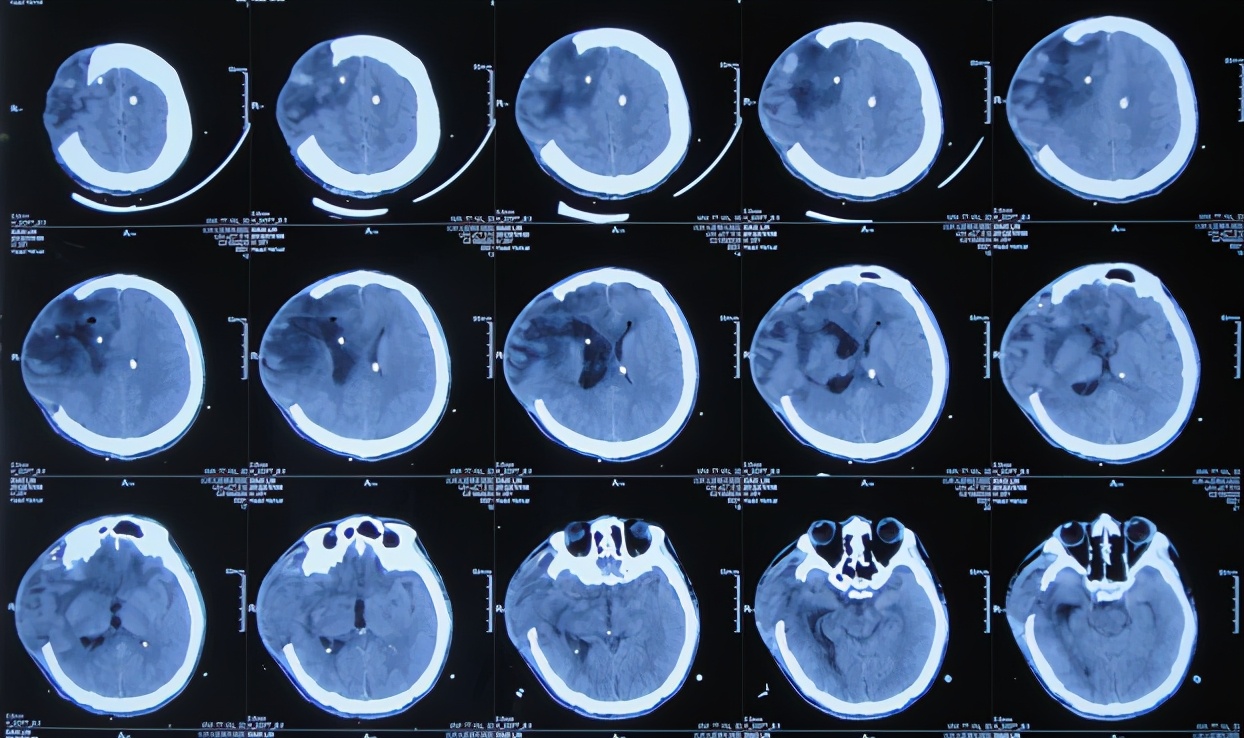

脑脊液培养提示为鲍曼不动杆菌,于2020年12月26日,查头颅CT( 图-8 )后,进行了脑室外引流术,引流出脑脊液内有大量脓液;因颅内感染严重该院医生建议患者家属转至北京北亚骨科医院的李小勇脑脊液科进一步治疗。

图-8: 2020年12月26日头颅CT